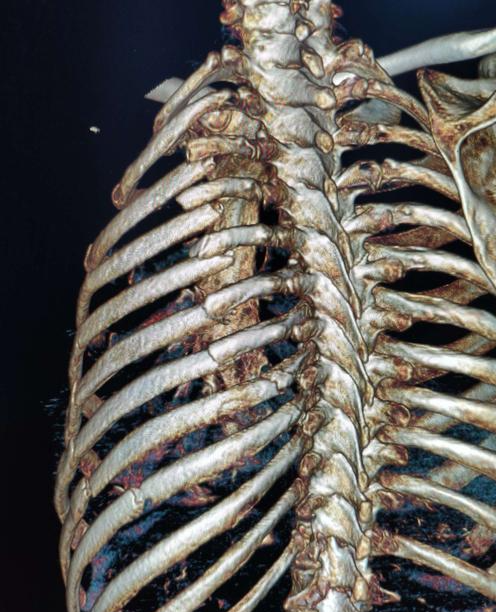

如果是严重外伤导致的锁骨骨折,也可能伴有周围其它部位的骨折。

例如肩胛骨和肋骨的骨折,此时需要对周围的骨头进行检查,并消除危险因素。

由于锁骨的位置特殊,当巨大的外力导致锁骨骨折时,可能会损伤肺部和周围的神经血管,这时,很容易形成血胸和气胸,或者臂丛神经损伤。